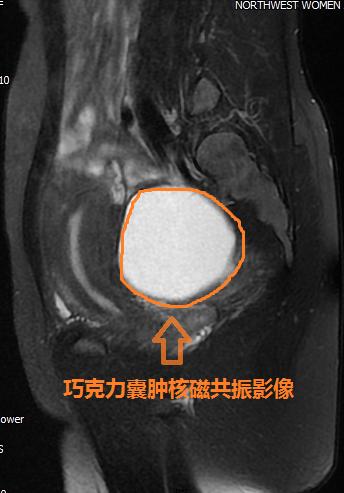

核磁共振矢状位最大切面T2压脂图像